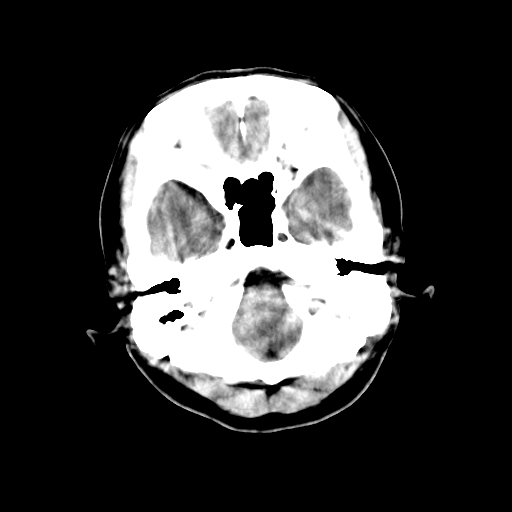

标题: CT23995:女,42岁,前额部外伤1小时,伤后头痛。 [打印本页]

女,42岁,前额部外伤1小时,伤后头痛。

头颅ct平扫未见异常

未见明显异常!

颅脑ct平扫未见异常,必要时复查